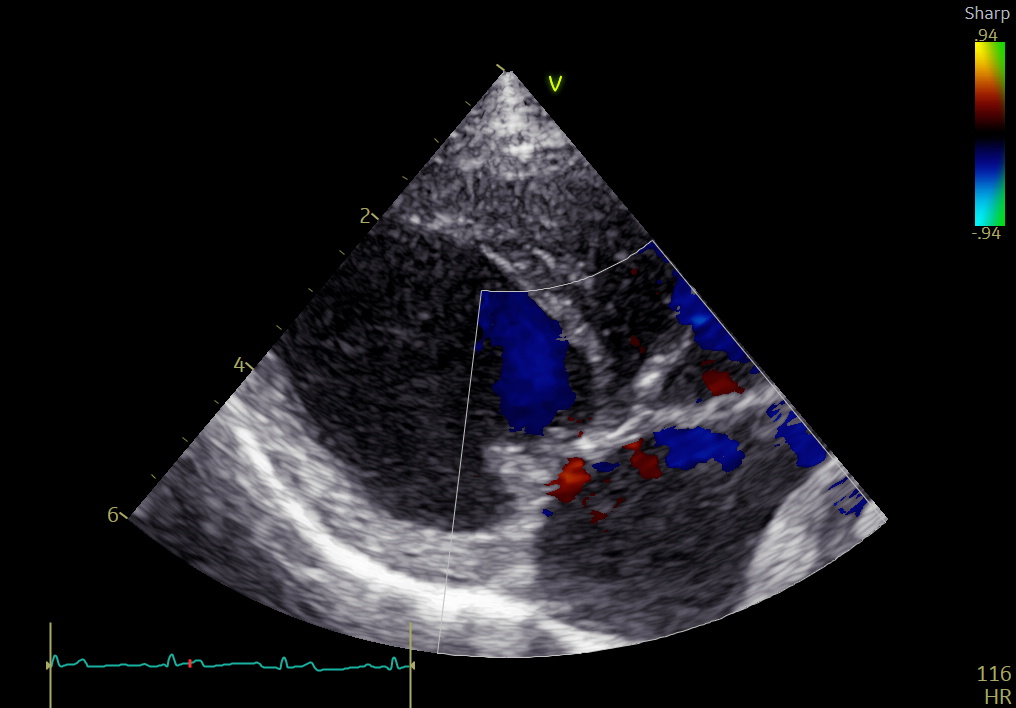

心臓超音波検査では、

• LA/Ao:2.70

• LVIDDN:2.37

• 重度僧帽弁逆流

を認め、左房・左室ともに著明な拡大が確認されました。

手術前